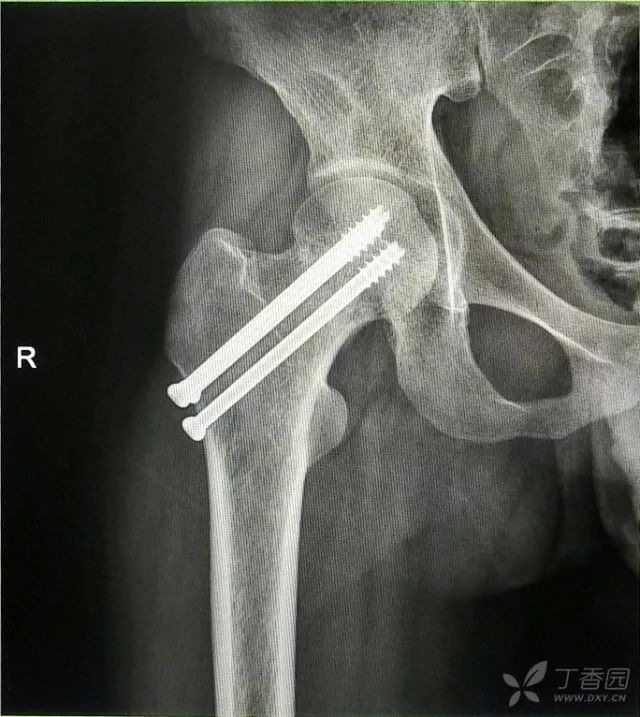

辅助检查:CT 检查提示右侧股骨颈骨皮质不连续,可见透亮骨折线及碎骨片影,断端错位、成角,周围软组织肿胀;右侧髋臼后下缘及左侧耻骨上支骨皮质不连续,断端未见明显错位;右侧髋臼后缘见类圆形稍低密度影,大小约 5*9 mm,边界清楚,边缘见硬化边;右侧髋关节在位,关节间隙未见明显变窄。

初步诊断:右股骨颈骨折(经颈型)

2. 倒数第二次的复位仍是欠缺一点

3. 再努力一把就基本成了